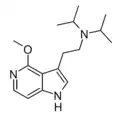

7-Aza-5-MeO-DiPT (P-19) | N-[2-(5-methoxy-1H-pyrrolo[2,3-b]pyridin-3-yl)ethyl]-N-(propan-2-yl)propan-2-amine | |

|

(R)-69 | 3-[(5R)-5-methyl-1,2,5,6-tetrahydropyridin-3-yl]-1H-pyrrolo[2,3-b]pyridine | |

|